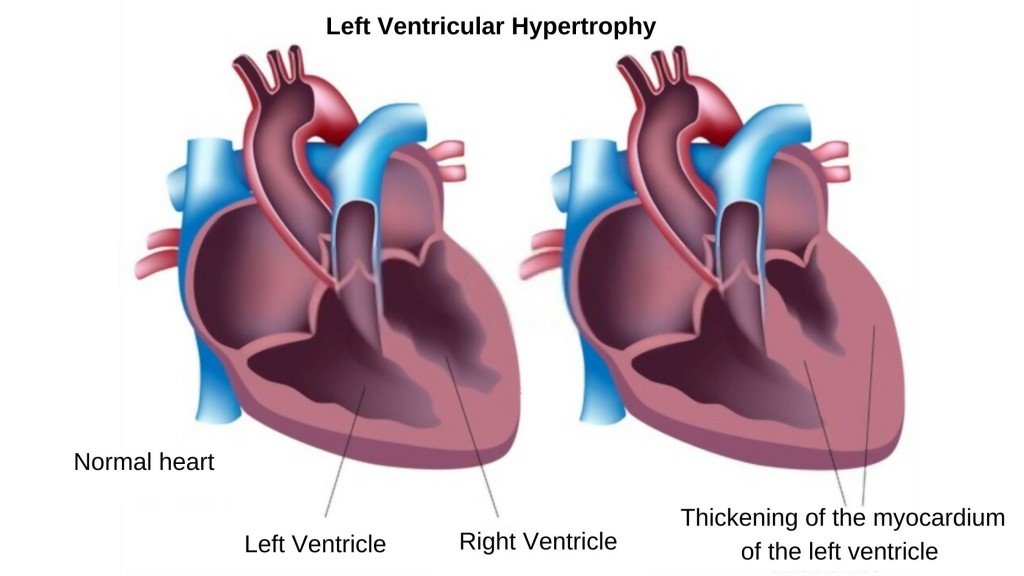

Left ventricular pumping function, including ejection fraction, wall motion, and wall thickening